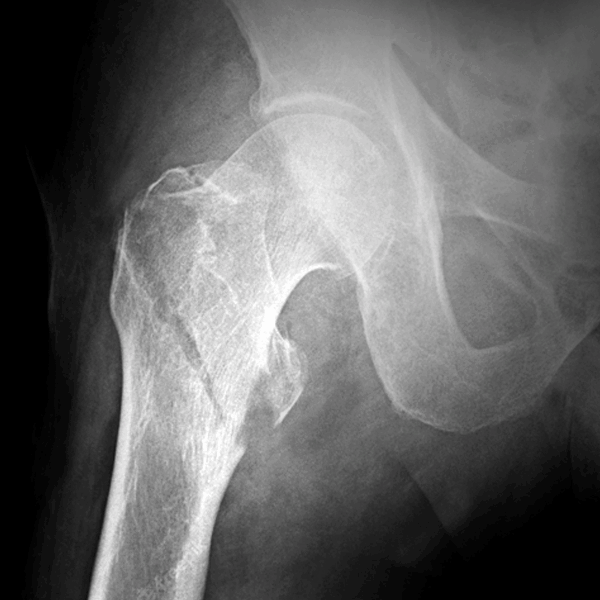

Radiografías simples de las articulaciones

(Clavícula, omóplato, mano, pie, dedos, huesos largos y mandíbula)

- Permiten la evaluación de fracturas, tumores, infecciones, alteraciones estructurales y enfermedades degenerativas.